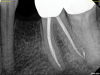

The quality of the initial NSRCT is inversely associated with RETX outcomes, with poorer quality initial treatment tied to more predictable retreatment (Figure 6 through Figure 8).23 Inadequate quality of the initial NSRCT (eg, untreated anatomy, under-instrumentation, ledged and underfilled canals, and overextended obturation) was associated with greater predictability following RETX. However, if clinicians cannot identify and correct the mistakes made in the previous root canal therapy, it becomes more challenging to improve treatment outcomes.23

Fig 7. Identifiable inadequate NSRCT is associated with predictable RETX. Fig 6: Preoperative periapical radiograph showing AP, tooth No. 20. Fig 7. Postoperative periapical radiograph. Fig 8. Six-month follow-up periapical radiograph showing a significant decrease in size of the AP.

Figure 7

Fig 8. Identifiable inadequate NSRCT is associated with predictable RETX. Fig 6: Preoperative periapical radiograph showing AP, tooth No. 20. Fig 7. Postoperative periapical radiograph. Fig 8. Six-month follow-up periapical radiograph showing a significant decrease in size of the AP.

Figure 8